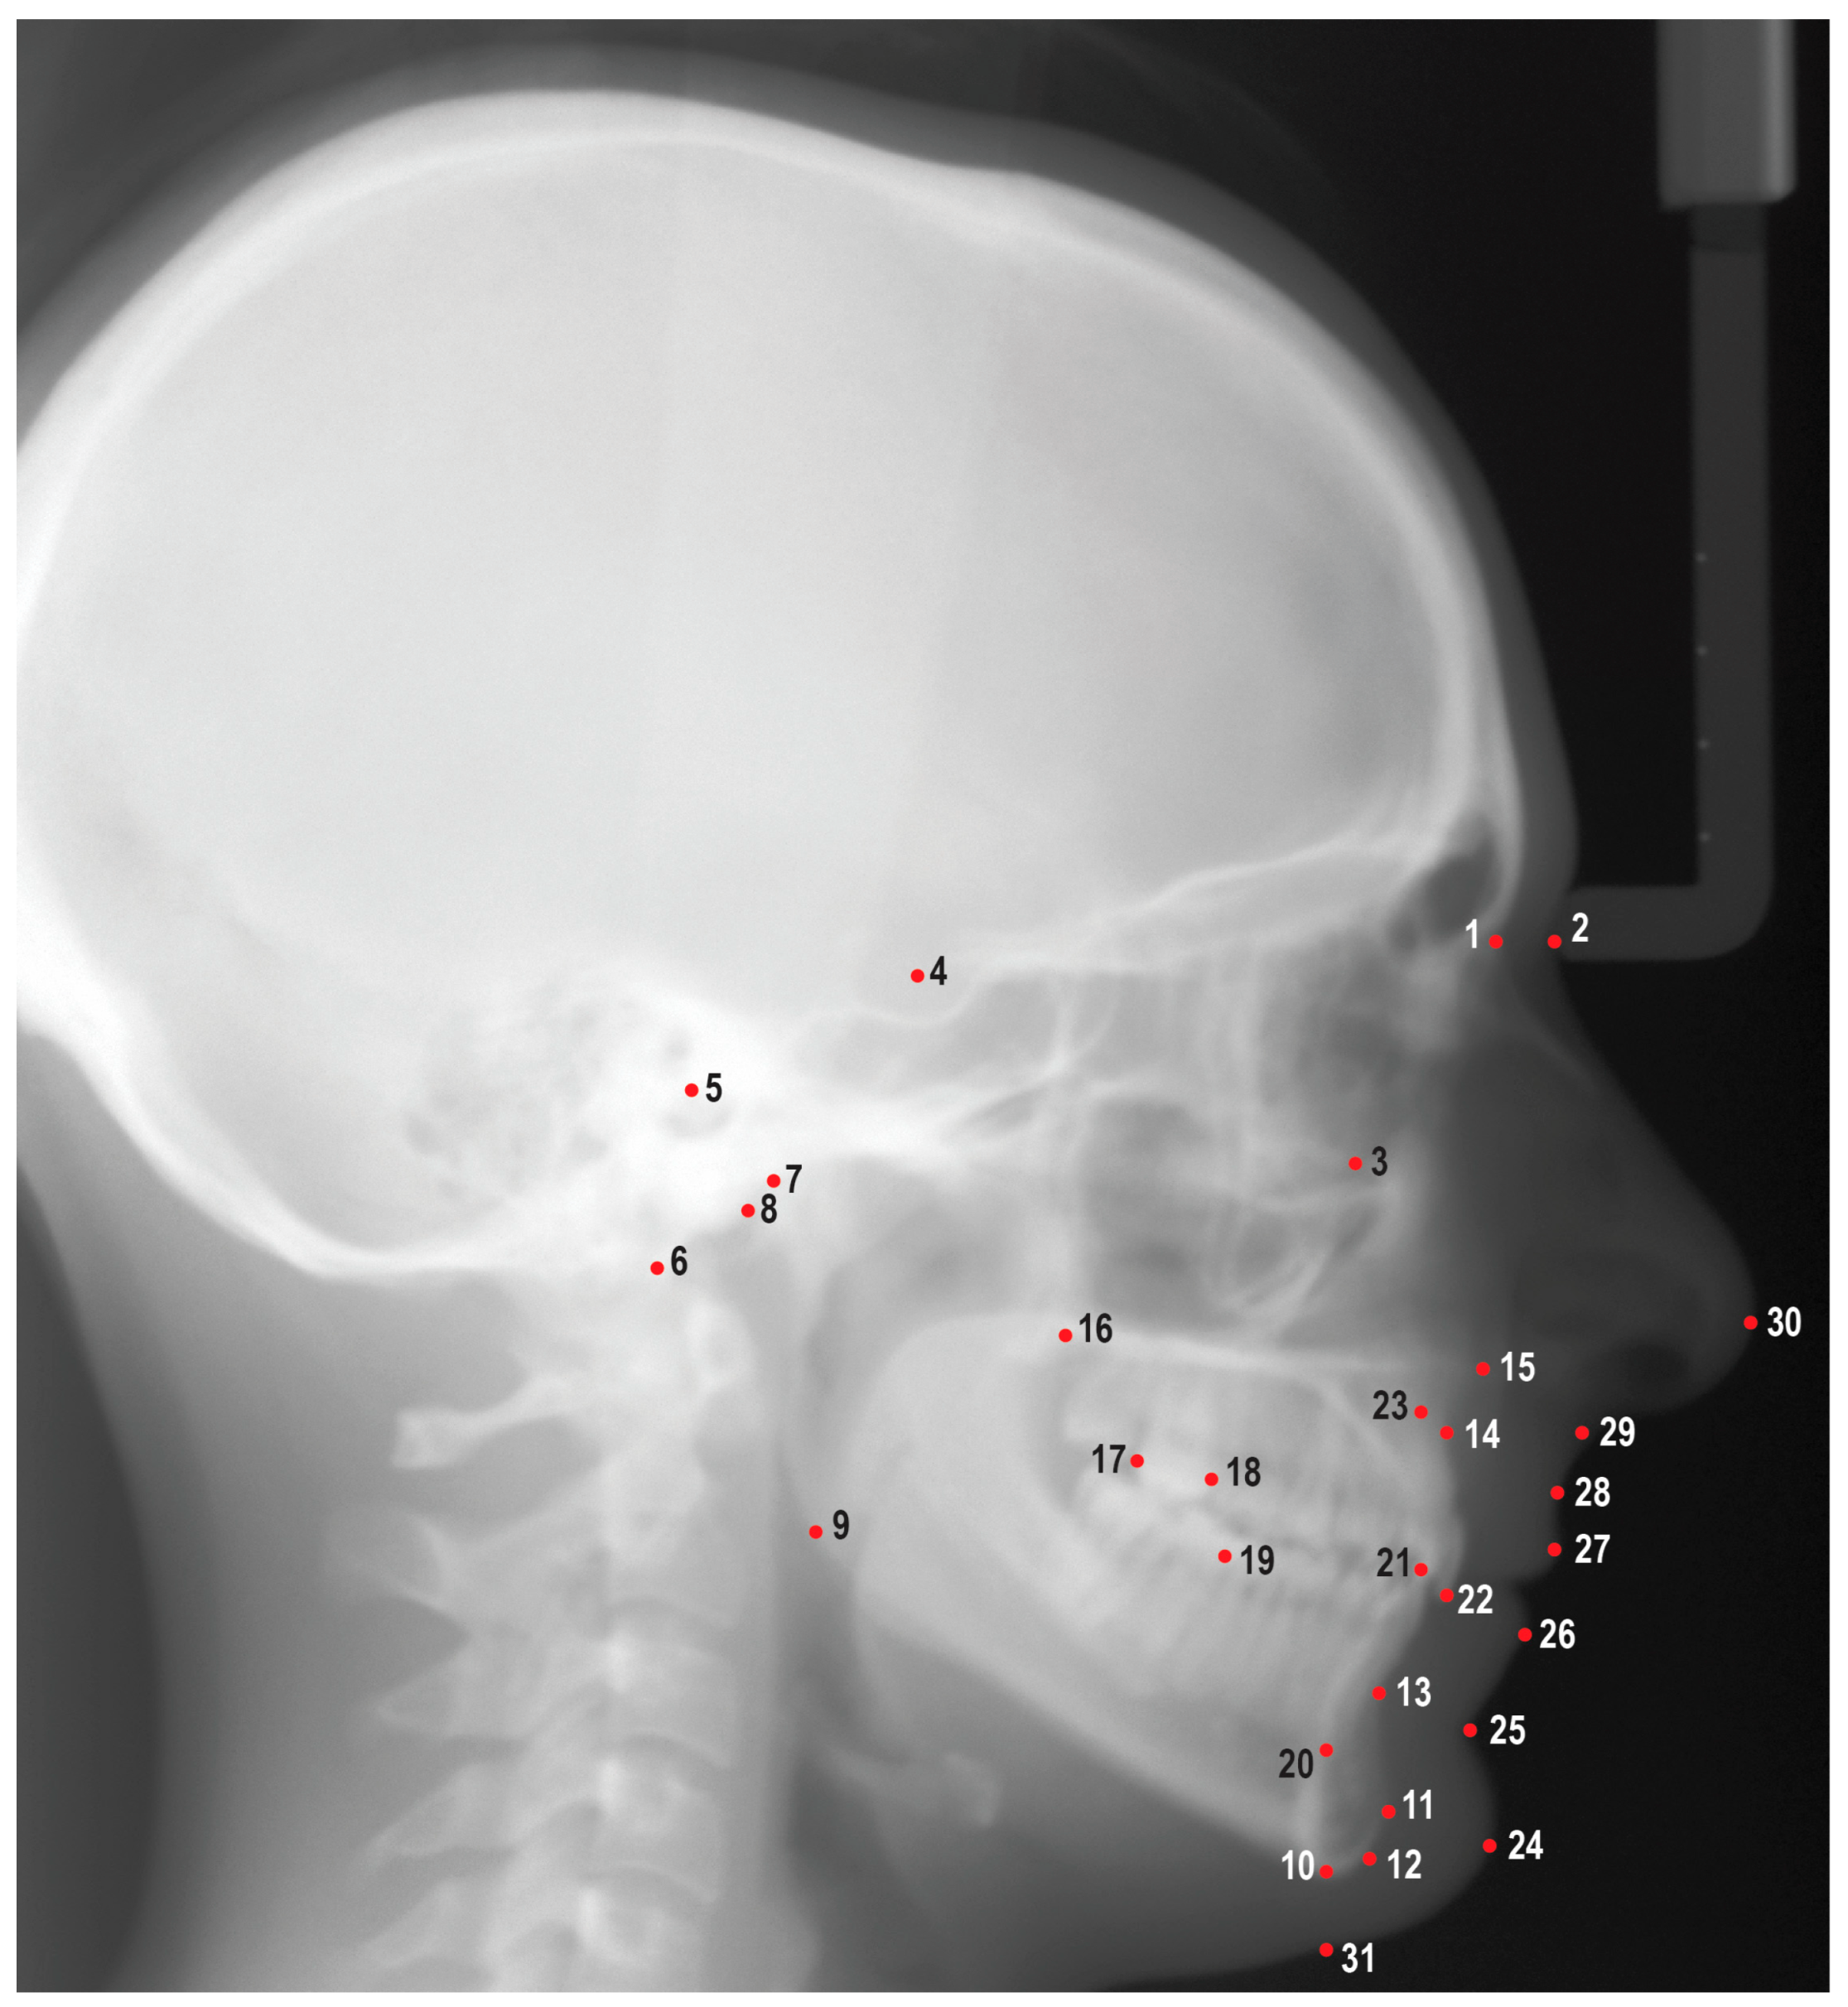

2.2. Data Collection

2.3. Software